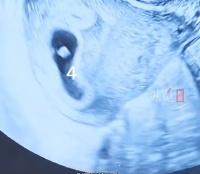

带着疑惑,夫妻二人一同来到医院,经过全面检查,真相终于浮出水面。张先生不仅近一个月出现排尿困难、淋漓不尽的不适症状,精液检查结果更是让人揪心:精子DNA碎片率高达31.26%,远超医学上>30%的高风险临界值,意味着精子存在严重遗传损伤;同时正常精子百分比仅3%,精子前向运动活力严重不足。

医生解释,精子DNA碎片率,是衡量精子质量的核心指标,碎片率越高,精子质量越差,不仅会大幅降低受孕几率,即便成功怀孕,也会增加胚胎发育不良、流产的风险,这也是张先生夫妻备孕屡屡失败的核心原因。

• 精子DNA碎片率:从31.26%直接降至17.74%,彻底脱离备孕高风险区间,达到安全生育标准;